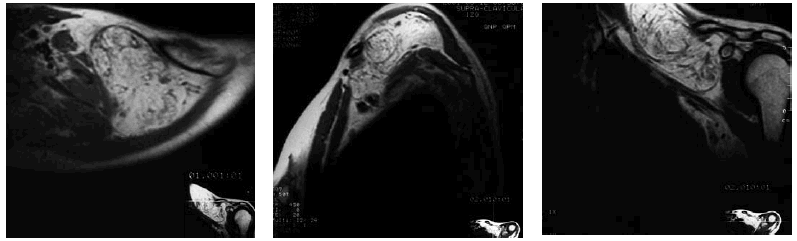

Se decide realizar exploración con resonancia magnética nuclear (RMN) obteniéndose las imágenes de las figuras 1 y 2.

Fig. 1. Cortes axial, sagital y coronal del hombro izquierdo con imágenes potenciadas en T1. Se observa un efecto de masa hiperintenso con imágenes lineales hipointensas en su interior. No presenta cápsula y hay mala definición de su límite inferior que se continúa insensiblemente con la grasa del hueco axilar.